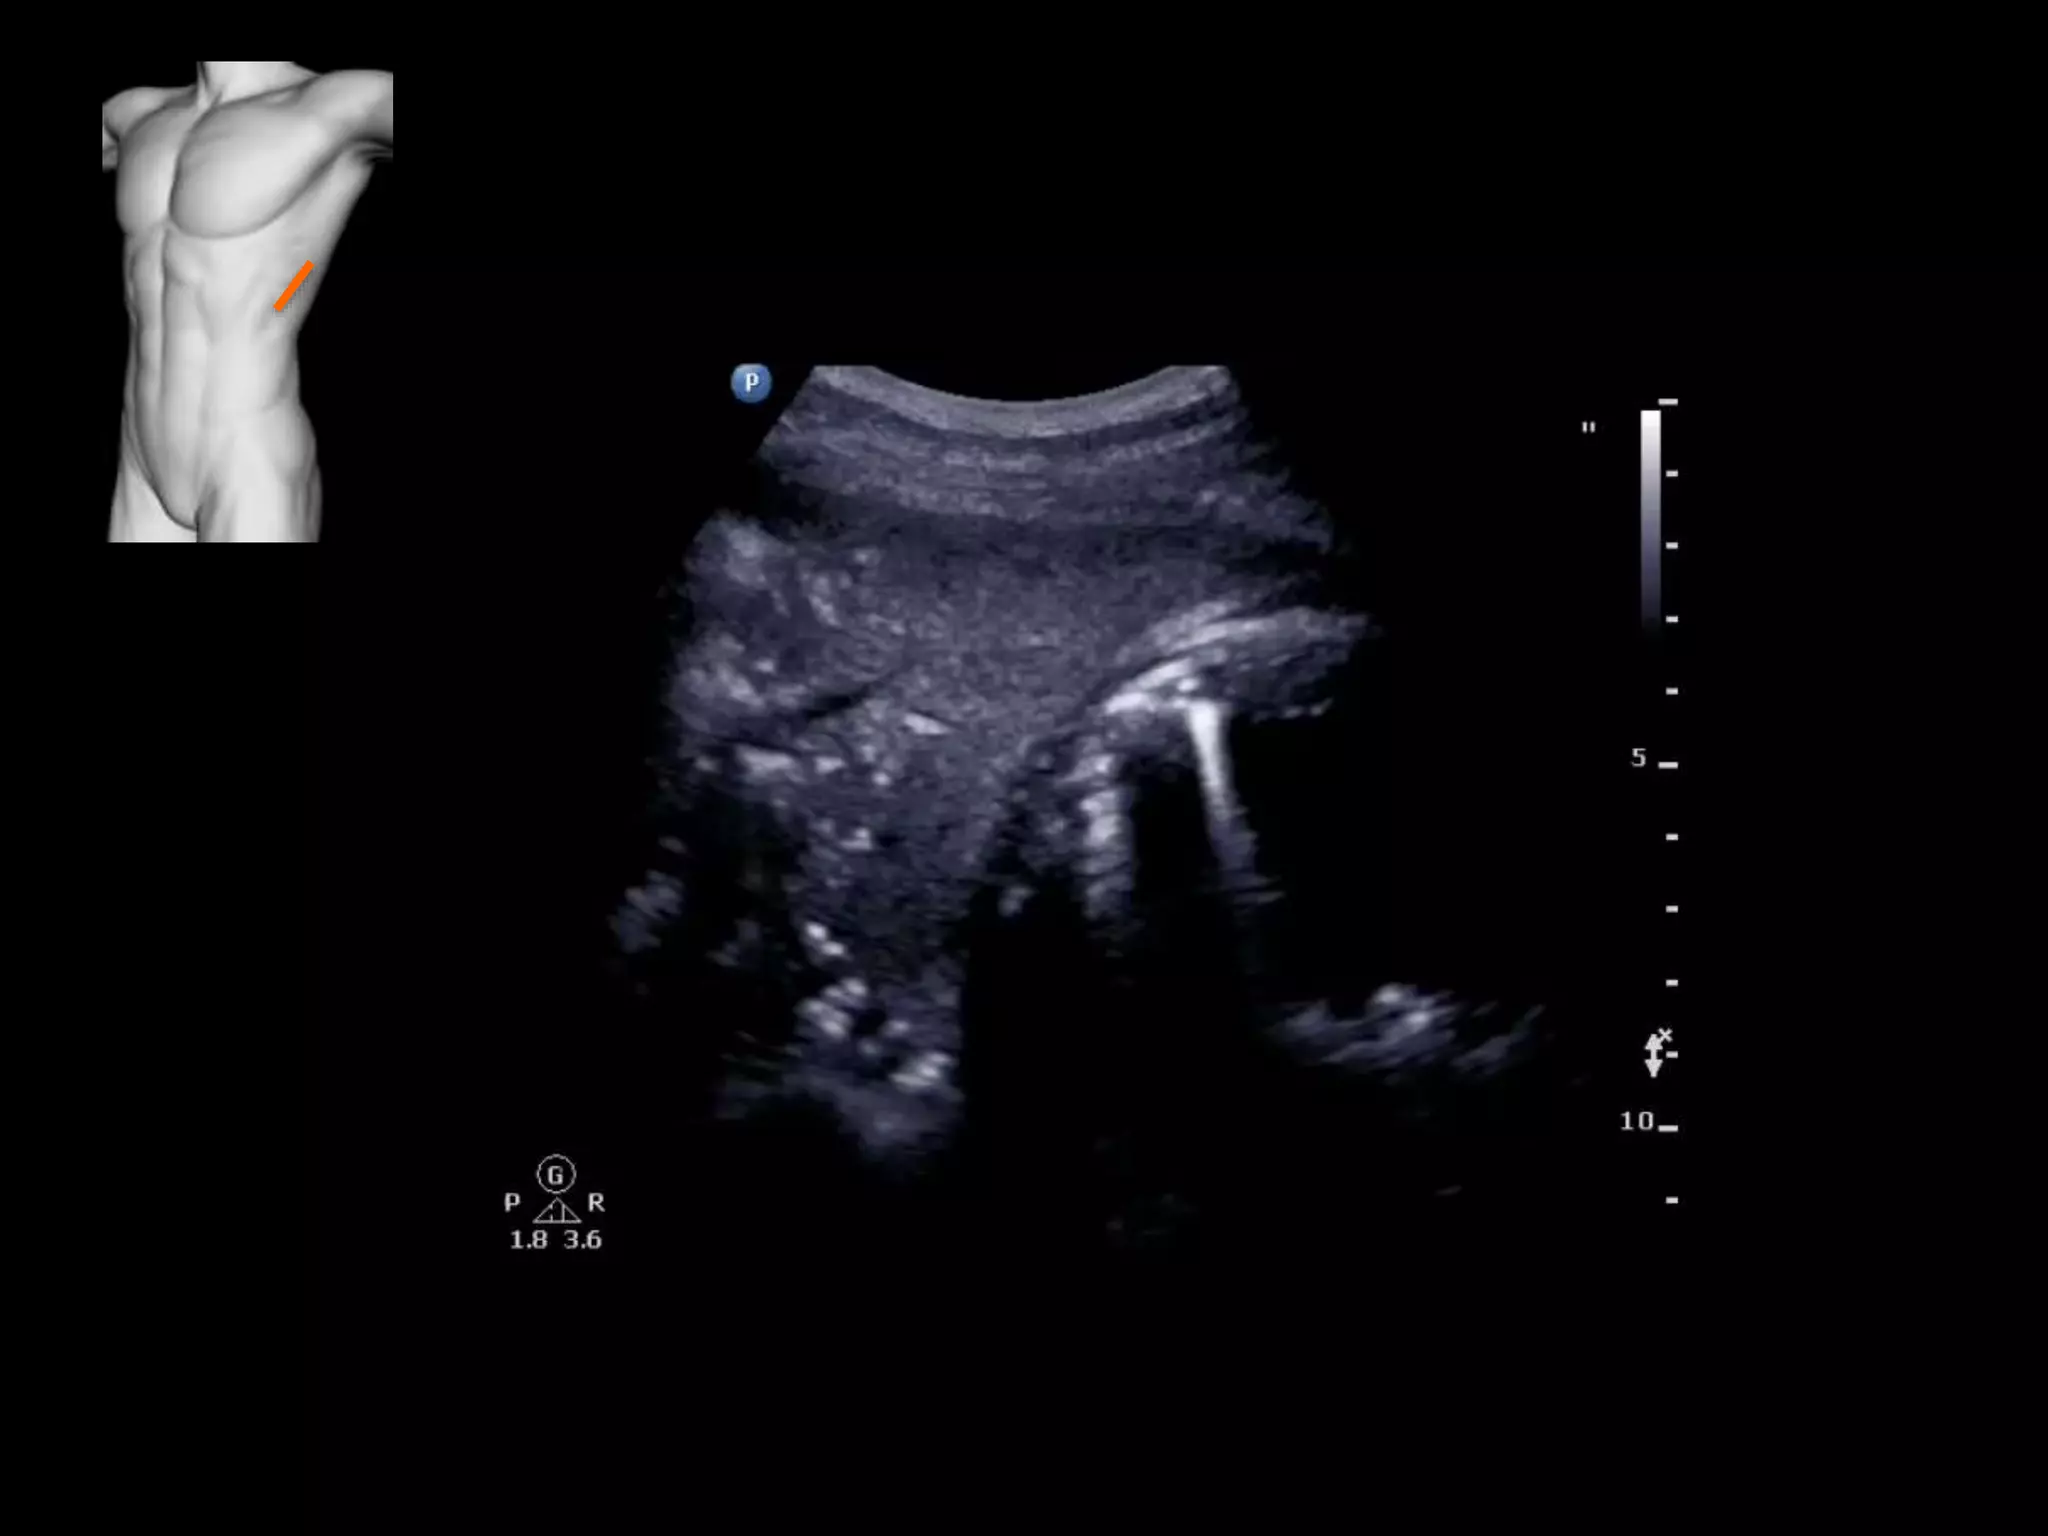

Case study 2

• Young man with history of sarcoma

• Increasing shortness of breath

• Large pleural effusion

• Fine echogenic debris suggests exudate,

infection or blood

• Nodules on pleural surfaces suggest

malignancy

• Describe spine sign and descending aorta

visualisation

• Consolidation

• Hepatisation, air bronchograms, shred sign